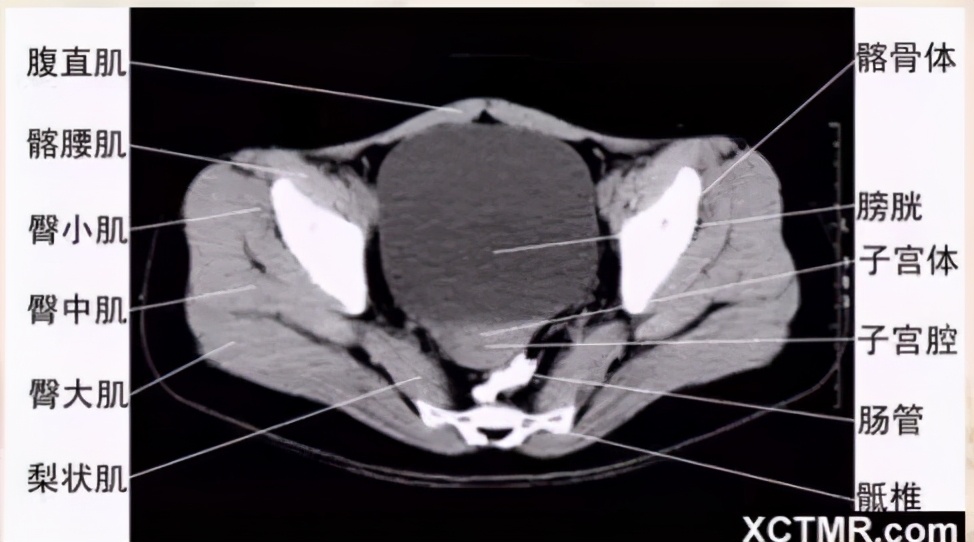

女性盆腔CT断层